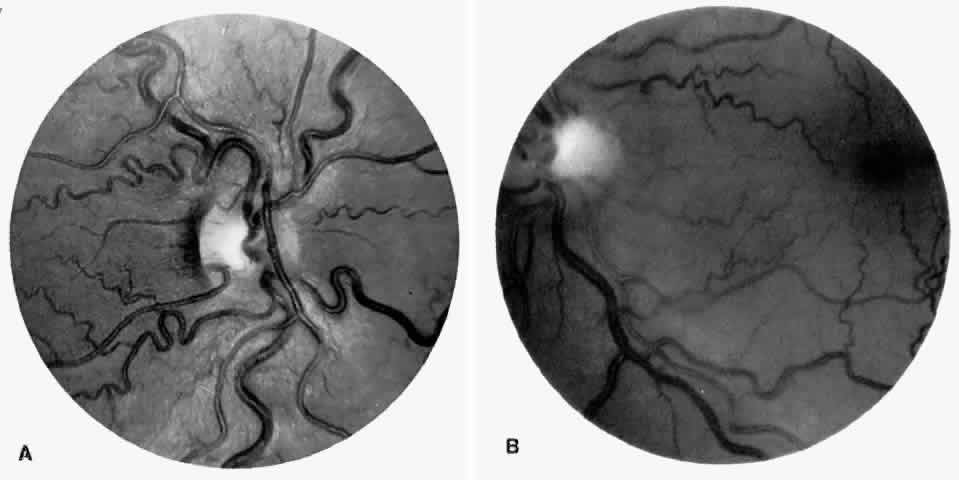

Angioid Streaks

Angioid streaks occur in association with sickle cell disease, with an overall incidence of less than 6%.72–75 The changes are more common in patients with homozygous sickle cell anemia and are age-dependent, occurring in 2% of sickle cell anemia patients less than 40 years of age versus 22% in those who are more than 40 years of age (Fig. 5).76

Fig. 5. A 45-year-old man with homozygous sickle cell anemia and angioid streaks (arrows).

Unlike the angioid streaks seen in patients with pseudoxanthoma elasticum, choroidal neovascularization and disciform disease are uncommon in association with sickle cell disease. Elastic tissue degeneration, as is seen in pseudoxanthoma elasticum, has not been demonstrated in the skin biopsy specimens of sickle hemoglobinopathy patients with angioid streaks.73,75 Initially, the etiology of angioid streaks in sickle cell disease was hypothesized to be secondary to iron deposition due to chronic hemolysis, causing brittleness of Bruch's membrane. Histopathologic examination of angioid streaks in a patient with homozygous sickle cell anemia, however, revealed heavy calcification of Bruch's membrane without evidence of iron or hemosiderin.77